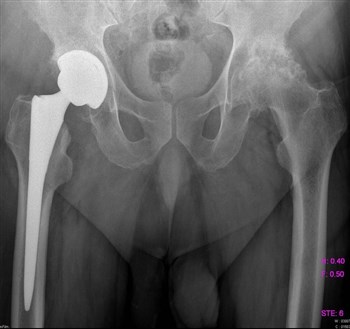

Артроз тазобедренного сустава

Патология, при которой разрушаются хрящевые ткани, приводит к ограничению подвижности в тазобедренном суставе на запущенной стадии.

Пациенты все чаще жалуются на боли в паху, колене и ноге, а также на скованность движений и нарушение походки. Чаще всего этим недугом страдают женщины старше 40 лет.

Боль может локализоваться как в одной, так и в обеих ногах.

Для постановки диагноза проводят диагностику, которая включает:

- МРТ;

- Рентгенографию;

- Компьютерную томографию.

Эти методы помогут определить стадию заболевания и состояние мягких и костных тканей.

Если заболевание не хроническое, лечение может проводиться с помощью парацетамола без хирургического вмешательства. Врач назначает курс массажа, лечебной гимнастики и регулярный контроль ортопеда. При ноющих болях могут быть прописаны болеутоляющие препараты, такие как Кеторол и Диклофенак.